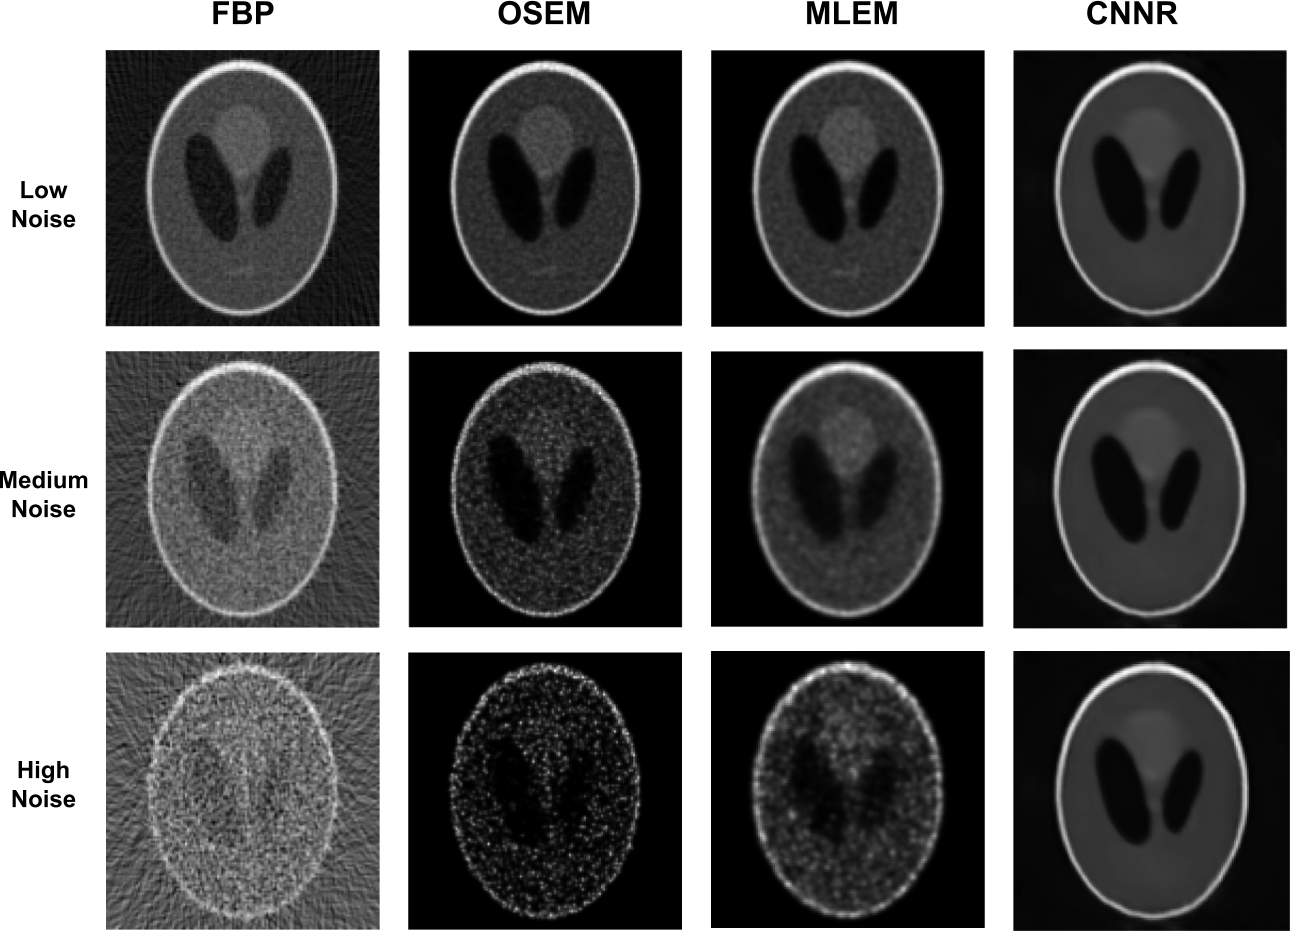

To assess the performance of the proposed CNNR method versus existing methodologies, the Mean Square Error (MSE), Mean Absolute Error (MAE), Structural Similarity (SSIM) Index [18], and the Pearson Correlation Coefficient (PCC) [19] were used. As the results show, Table I, the proposed CNNR method (highlighted in bold) outperforms all other methodologies, especially in the medium and high noise scenarios.

Refer to caption

Figure 4: Evaluation and comparison of the proposed CNNR method versus the OSEM, MLEM and FBP methods. The results obtained using CNNR compare favourably to those obtained with the widely used FBP, OSEM and MLEM methods.

In this paper, we propose a new method to perform SPECT image reconstruction using convolutional neural networks and demonstrate the effectiveness of the method. For the training of the proposed convolutional neural network, we randomly created and used 600,000 software phantoms. Furthermore, we used existing methods, such as FBP, OSEM and MLEM applied to Shepp-Logan software phantoms 2, to compare with the proposed method to assess the performance of the method. The results of FBP, OSEM, MLEM and the proposed method are outlined Table I and Figure 4. The proposed CNNR method outperforms all other methods in reconstructing the Shepp-Logan software phantoms, as the results show, particularly in medium and high noise conditions. Even though the conditions the proposed method is tested and the results presented are suitable to demonstrate the proposed CNNR method capabilities, compared to existing methods, additional experimentation is needed with real phantoms. These experimentations will evaluate the implied use of the proposed method in clinical studies.